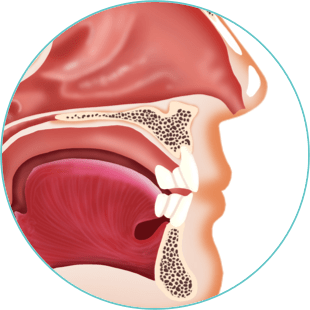

Nose & Mouth

Lorem ipsum dolor sit amet, consectetur adipiscing elit. Etiam nec aliquam ex, eget consequat est.

- Morbi venenatis non lectus sit amet tincidunt

- Gellentesque sit amet eleifend velit

- Vestibulum fermentum cursus facilisis

- Etiam nec aliquam ex, eget consequat est.

Lorem ipsum dolor sit amet, consectetur adipiscing elit. Ut quis libero eros. Vestibulum fermentum cursus facilisis. Pellentesque sit amet eleifend velit. Donec consectetur posuere tortor a finibus.